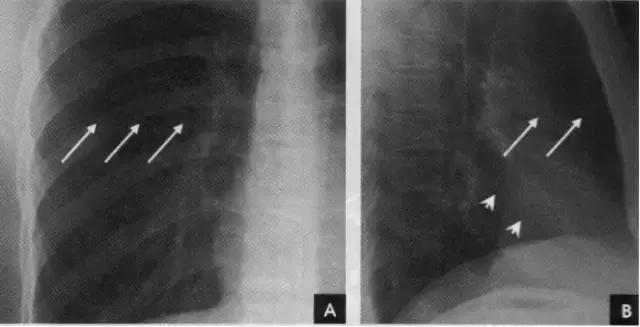

(二)叶间胸膜转折(叶间裂)

1、斜裂 一般在正位片上不能显示.在侧位片上表现为自后上斜向前下的线条状阴影:右德斜裂的后端起始于第4、5胸椎水平,斜向前下方走行,止于膈面距前缘2~3cm处,与膈顶部的水平面约成50°角;左侧斜裂后端起始点较右侧稍高,在第3~4后肋端水平,因而其倾斜度也较右饲稍大,前下端达肺的前下角处,与膈顶水平面约成60°角。叶间胸膜面通常略有弯曲,斜裂上半部稍斜向外,下半部稍斜向内,故在侧位片上可成s形。

2、横裂又称水平裂,约70%的人正、撼位胸片均可显影。在正位片上表现为右中肺野横行细线状阴影,从第6肋腋部水平自外向内延伸.并止于肺门外lcm处。可向上或向下倾斜10:左右或略成曲线;在侧位片上,横裂起白斜裂中部,向前呈水平方向走行达前胸壁。其位置的改变可作为判断肺体积变化的标志(如上图)。